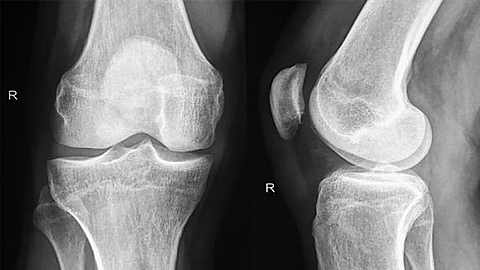

Nhóm nghiên cứu tại NU đã bắt đầu triển khai các thí nghiệm tập trung vào tái tạo xương hoặc sụn, trong đó các "ma trận" này bao quanh những tế bào sẵn có hoặc kết chặt xung quanh các nhân tố phát triển (gồm các protein chức năng thường được đưa tới các bộ phận trong cơ thể để hỗ trợ quá trình tái tạo khi có tổn thương).

| Điểm ưu việt ở phương pháp này là các "ma trận" được tạo ra từ các vật liệu hữu cơ. (Nguồn: Medical News Today). |